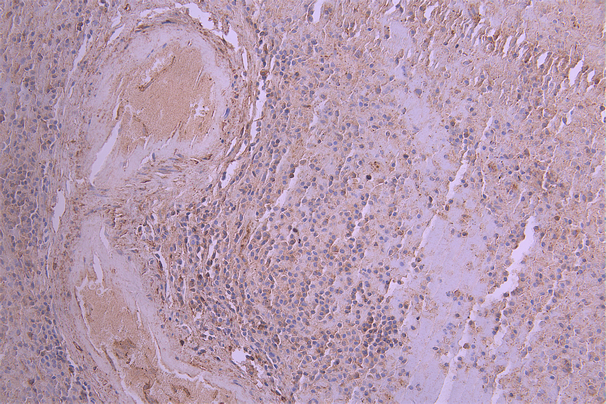

IHC image of CSB-RA011664MA3HU diluted at 1:50 and staining in paraffin-embedded human tonsil tissue performed on a Leica BondTM system. After dewaxing and hydration, antigen retrieval was mediated by high pressure in a citrate buffer (pH 6.0). Section was blocked with 10% normal goat serum 30min at RT. Then primary antibody (1% BSA) was incubated at 4°C overnight. The primary is detected by a Anti-Human lgG, Fcy Fragment Specific labeled by HRP and visualized using 0.05% DAB.